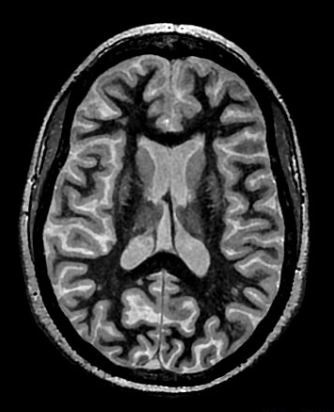

Figure 1. White matter nulled brain image

• Recovery Time: use a combination of TI and recovery time value to get a white matter nulled brain images (use the values in the GE protocol: FA = 8, TI = 400 and adjust recovery time such that Temp Resolution = 3 seconds). Note that the minimum and maximum values are displayed as a tool tip when you hover the mouse over the Recovery Time field.